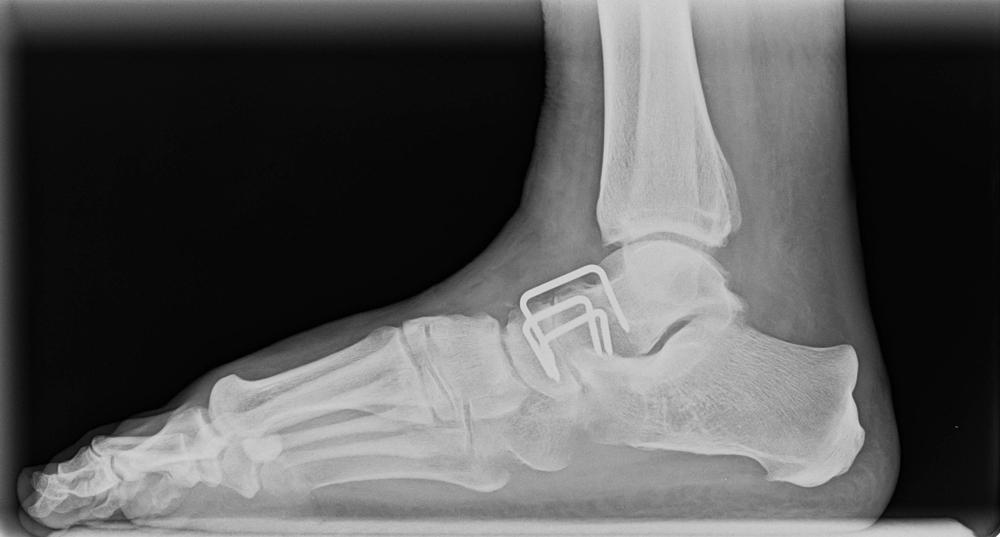

Arthrodesis adalah sebuah operasi yang merujuk pada prosedur medis untuk menyatukan dua tulang pada persendian. Dalam pelaksanaannya, dokter ahli bedah ortopedi akan meluruskan sendi yang rusak secara manual, mengangkat tulang lunak, dan menstabilkan tulang pada persendian tersebut agar bisa pulih secara bersamaan.

Umumnya, prosedur ini paling sering dilakukan untuk pergelangan kaki (ankle), kaki (foot), atau tulang belakang (spinal). Jika prosedur ini berhasil, persendian yang terdampak memang tidak bisa bergerak kembali, tetapi tulang yang menyatu pada persendian tidak akan terasa sakit.

Selain itu, tepat sebelum operasi, Anda mungkin akan menjalani beberapa tes pencitraan, termasuk CT scan, ultrasound, X-ray, dan magnetic resonance imaging (MRI).